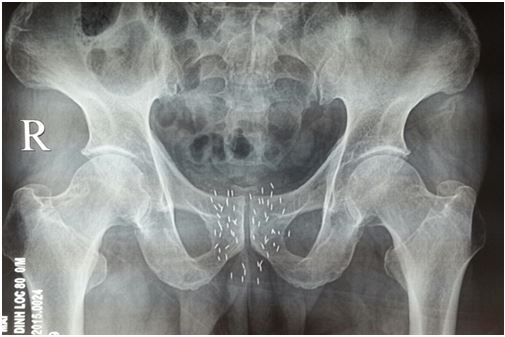

• Chụp XQ khung chậu thẳng: vị trí kim được cắm tốt

Về lâm sàng: Bệnh nhân có tụ máu nhẹ tầng sinh môn; ăn ngủ, sinh hoạt tốt; không sốt, không đái buốt, không đái rắt.